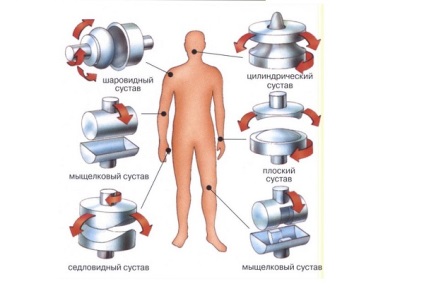

Osztályozási és típusok

A fejlesztés az emberi test, életmód, a mechanizmusok közötti interakció az ember és a környezet, annak szükségességét, hogy végezze el a különböző fizikai tevékenységek és kap különféle ízületek. Osztályozása ízületek és fő elvek három csoportba oszthatók: a felületek száma, az alak a csont vége, a funkcionalitás. Róluk beszélni fogunk egy kicsit később.

Az alakja felületek

Alakzáró ízületek és csontok van formák különböző geometriai formák (henger, ellipszis, gömb). Attól függően, hogy ez a mozgás végezni körül egy, kettő, vagy három tengely. Tekinteni, mint egy közvetlen összefüggés a típusa és alakja a felületek forgatást. Ezután egy részletes osztályozását az ízületek formájában felületén:

- Hengeres közös - a felület henger alakú, körül forog egy függőleges tengely (a tengellyel párhuzamos, és csatlakozik a csont függőleges tengelye a test). Ez a faj lehet rotációs neve.

- Nyereg - képződik összekötő két felületek, mint a „ül” egymásra. Egy csont együtt mozog a második oldalról a másikra. Anatomy magában körüli forgás merőleges tengely: flexiós-kiterjesztés és elrablás-közelítést.

- Gömbcsukló - a felület alakja van golyó (egy domború, a másik homorú), amelyben az emberek, hogy a körkörös mozgás. Alapvetően forgás jön létre három egymásra merőleges tengely, a metszéspont a központja a fej. A különlegessége a nagyon kis számú kötegek, amely nem akadályozza a körkörös forgás.

- Lapos közös - lapos lezárás csontok közel azonos méretű, a kölcsönhatás a három tengely, a fő jellemzője - egy kis mozgási tartományán és szalagok körülvevő.

- Feszes (amphiarthrosis) - áll, különböző méretű és formájú csontok, amelyek szorosan kapcsolódnak egymáshoz. Anatomy - mozgásszegény, merev felület képviselt kapszulák, nem elasztikus rövid szalagok.

Tekintettel a fiziológiai jellemzők ízületek, hogy sok mozgását tengelyére. Összességében ez a csoport három típusa van:

- Egytengelyű - amely körül forog az azonos tengelyen.

- Biaxial - forgatás két tengely körüli.

- Többtengelyes - elsősorban az egész három tengely.